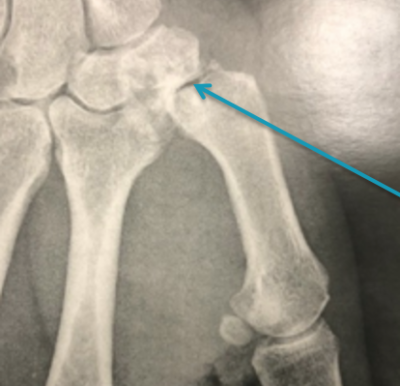

C’est l’arthrose de l’articulation reliant 2 os de la main appelés trapèze et premier métacarpien situés à la base du pouce au niveau du poignet. Cette articulation permet d’écarter le pouce des autres doigts et de le rapprocher de la paume de la main. L’arthrose associe l’usure du cartilage et la formation de petits fragments d’os gênant la mobilité d’une articulation appelés ostéophytes.

La localisation de la douleur oriente le diagnostic. Une simple radiographie de la main permet de confirmer le diagnostic.